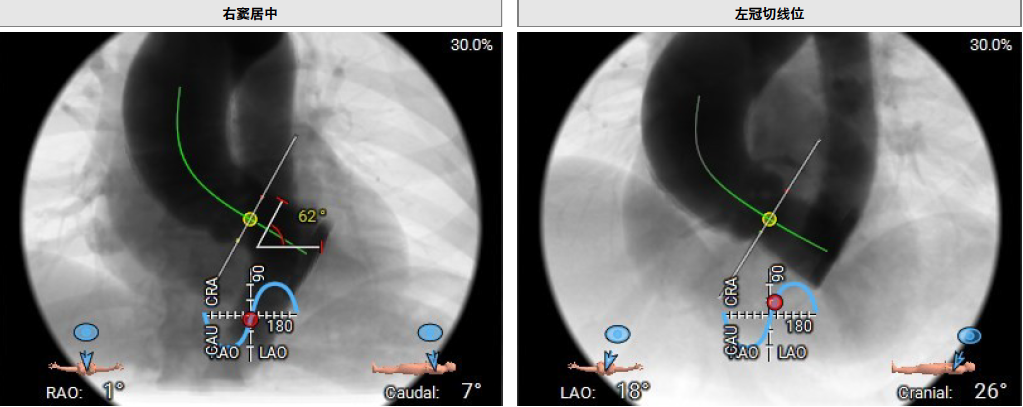

患者Type1 二叶瓣,右无融合,融合嵴钙化,钙化主要分布瓣叶缘和融合嵴处,无冠窦底钙化向下延伸至流出道4mm处。Annulus面积398mm²,LVOT面积400mm²,SOV 27.6-30.9mm,STJ高度21.3mm,内径29-32.7mm,瓣环角度62°,升主动脉扩张,左冠高度14.9mm,左冠瓣叶长度15.7mm,右冠高度15.8mm,右冠瓣叶长度9.2mm,模拟植入21#瓣膜VTC LCA 2.4mm,右侧髂内分叉处可见钙化,右侧髂外动脉最细为6.1mm,左侧髂外动脉最细为6.1mm,外周入路尚可。

释放体位 RAO 1° Cra 7° ;左冠切线 LAO 18° Cra 26°

左冠高度14.9mm,左冠瓣叶长度15.7mm,右冠高度15.8mm,右冠瓣叶长度9.2mm,模拟植入21#瓣膜VTC LCA 2.4mm

右侧髂内分叉处可见钙化,右侧髂外动脉最细为6.1mm,左侧髂外动脉最细为6.1mm,入路尚可。考虑右侧股动脉为主入路。